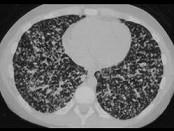

问题 女性,19岁,低热,盗汗,乏力,咳嗽1月余,CT检查如图,请选出最可能的诊断 ( )

选项 A.间质性肺炎 B.弥漫型肺癌 C.粟粒型肺结核 D.硅沉着病 E.大叶性肺炎

答案 C